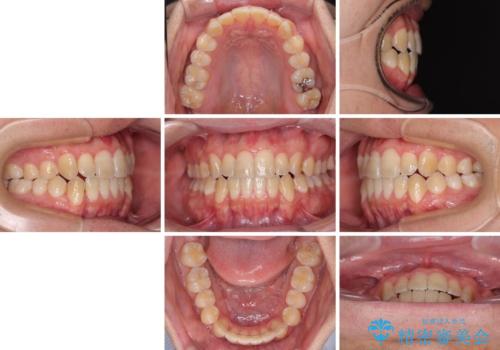

オープンバイトをインビザラインで矯正治療

- 1年11ヶ月

- 前歯の開咬を気にして来院された患者様です。

開咬の治療は、前歯を閉じるように動かすとともに、上下臼歯を圧下(骨内にめり込ませる)させることで進めて行きます。

インビザラインは臼歯の圧下を効果的に行えるため、インビザラインを用いて矯正治療を行うこととしました。